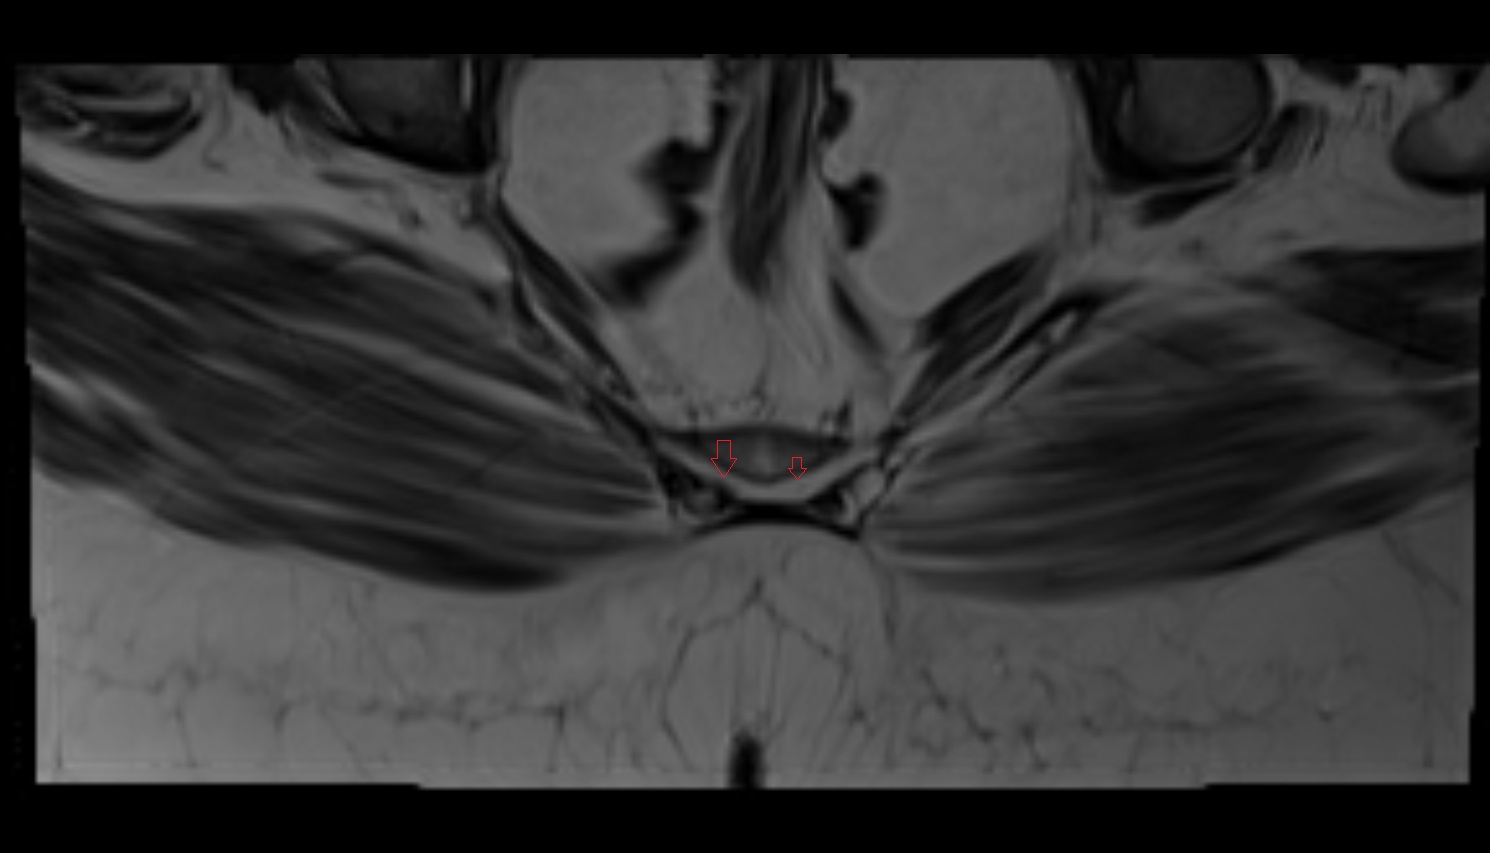

- Pubic symphysis

- Urinary bladder

- Uterus

- Vagina

- Mons pubis